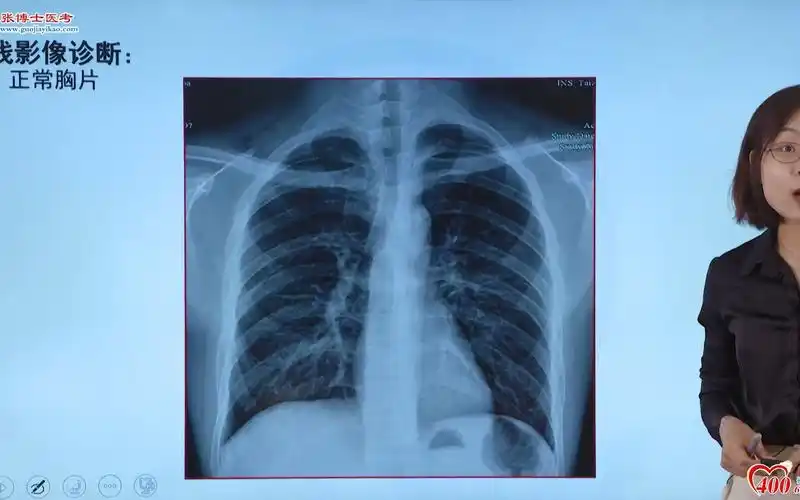

正常胸片

影像-正常胸片